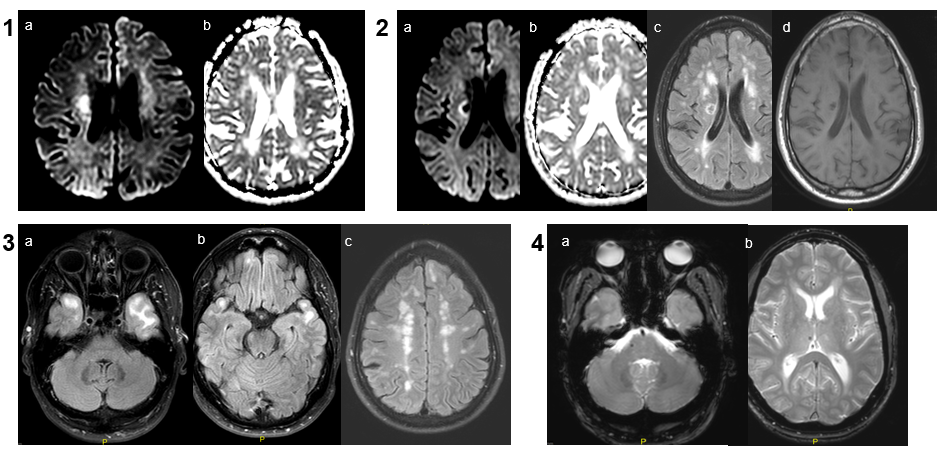

Se realiza estudio con RM cerebral (RM cerebral 1).

RM cerebral 1: 1.-Lesión isquémica aguda en cuerpo del núcleo caudado derecho que brilla en la difusión (a) y restringe levemente en mapa ADC (b). 2.- Infarto lacunar crónico adyacente a cuerpo del núcleo caudado derecho. No brilla en difusión (a) ni restringe en ADC (b). En FLAIR (c) se observa halo hiperintenso con centro de hiposeñal y en T1 (d) es hipointenso. 3.- FLAIR: Leucoencefalopatía confluente con afectación característica de polos temporales anteriores (a y b) y subcortical fronto-parietal (c). 4. Microsangrados crónicos en secuencia GE a nivel pontino derecho (a) y en tálamo homolateral.